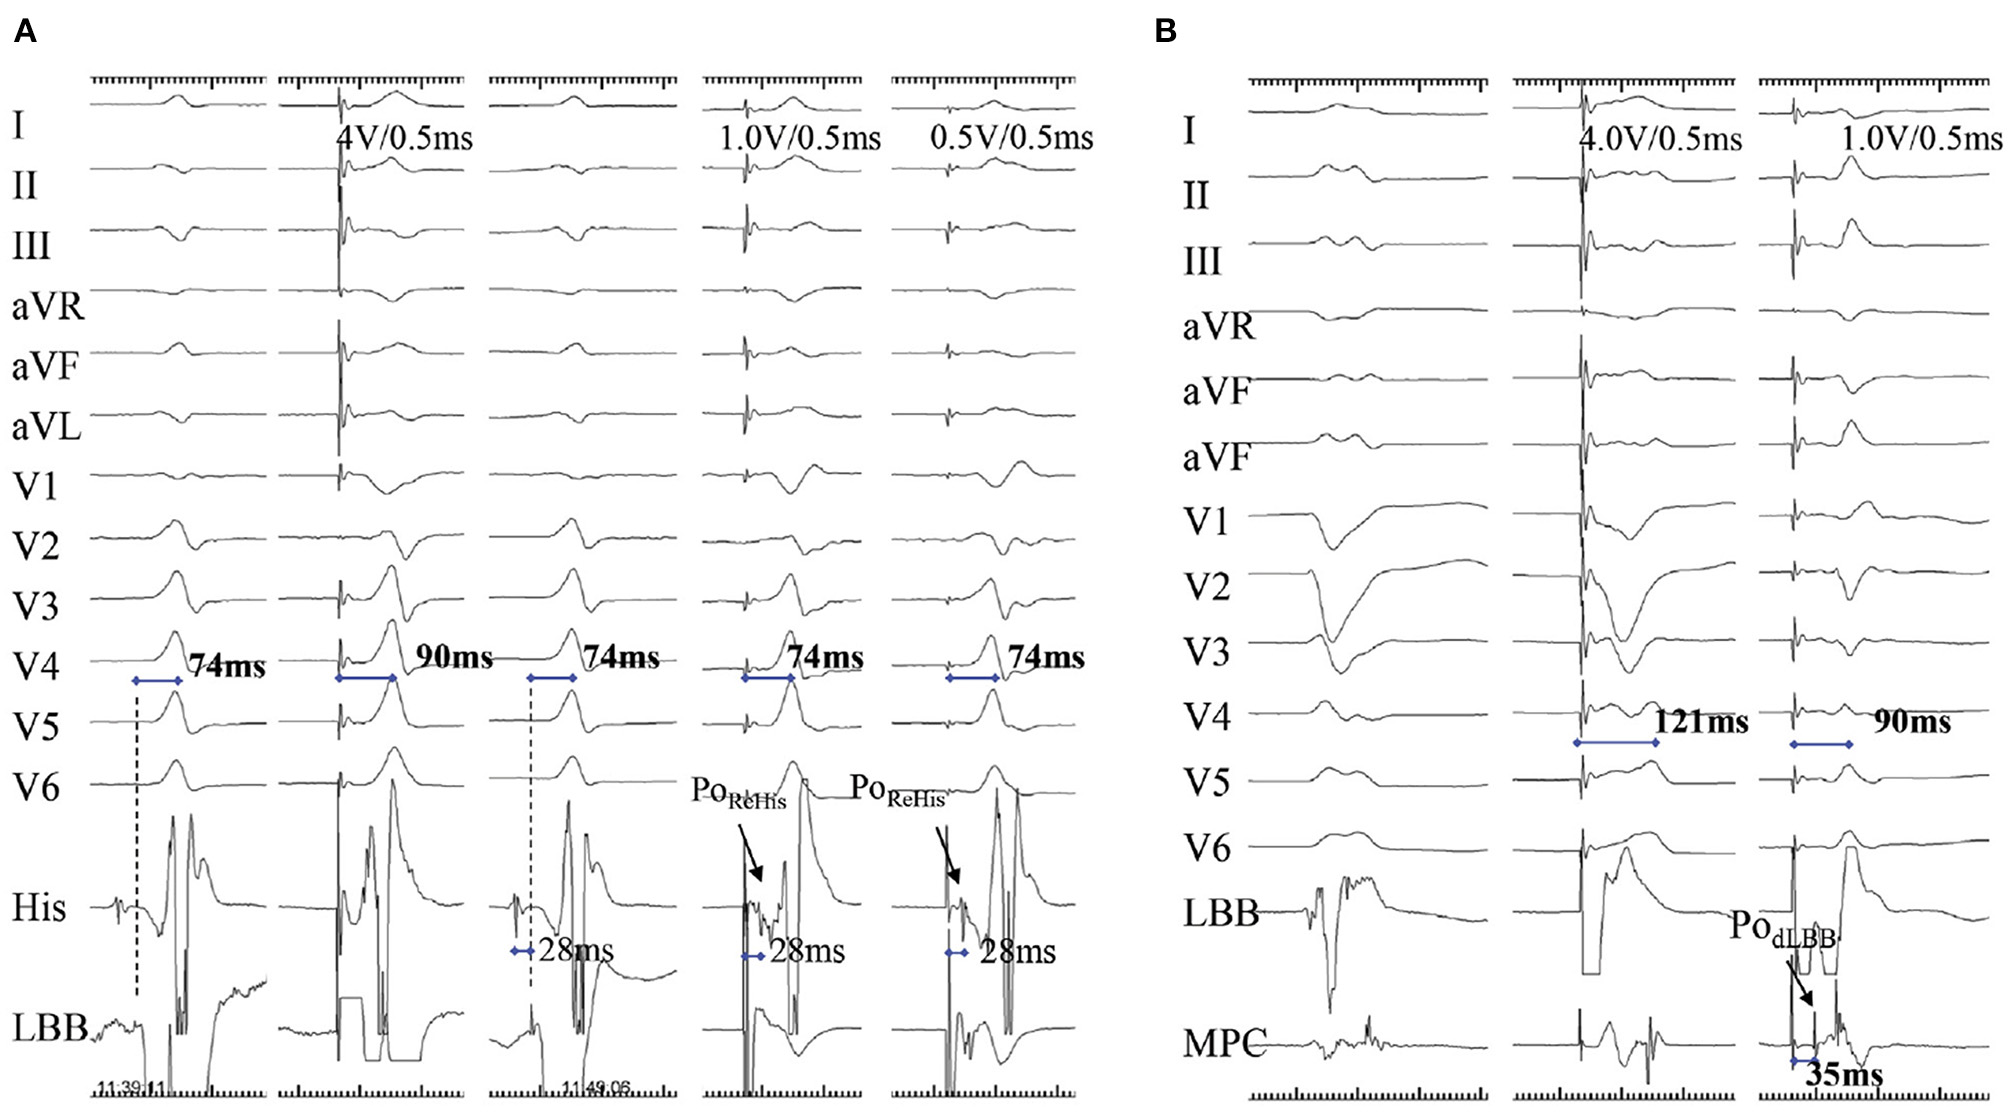

Reverse His potential can be recorded during low-output LBBP, via direct capture of LBB, in patients without conduction disease (Figure 5A). Alternatively, stimulus to atrial intervals can be assessed during unipolar pacing from the LBBP lead tip (cathode at the LBB) and unipolar ring (anode at right ventricular septum). Here, the stimulus to atrial intervals would be markedly shorter than right ventricular septal pacing (RVSP) (36). Moreover, the anterograde distal LBB potential can also be considered as an indicator of LBB capture and can be recorded by multipolar catheter placed distal to the LBBP lead (Figure 5B) (9).

Figure 5

A demonstration of direct LBB capture using retrograde His potential and anterograde distal left conduction system potential. (A) A case with narrow QRS wave. There is a small PoLBB and long pLVAT (90 ms) with septal pacing (first two beats). When the lead is advanced at a deeper site of septum, the non-selective and selective LBBP (last three beats) are visible, with larger PoLBB, shorter and constant pLVAT (74 ms), and PoRehis with stimulus to PoRehis interval of 28 ms at low and high outputs. (B) The PodLBB can be recorded after the ventricular EGM with MCP distal to the LBBP lead (first beat). The second beat shows the PodLBB remains after the ventricular EGM with 121 ms pLVAT during septal pacing, whereas the last indicates achievement of selective LBBP at a deeper site, PodLBB recorded ahead of ventricular EGM with shorter pLVAT (90 ms) (9). LBB, left bundle branch; pLVAT, peak left ventricular activation time; LBBP, left bundle branch pacing; MCP, multipolar placed; EGM, electrogram; PodLBB, distal left bundle branch potential; PoRehis, retrograde His potential.